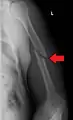

| Midshaft humerus fracture with callus formation | |

A transverse fracture of the humerus shaft